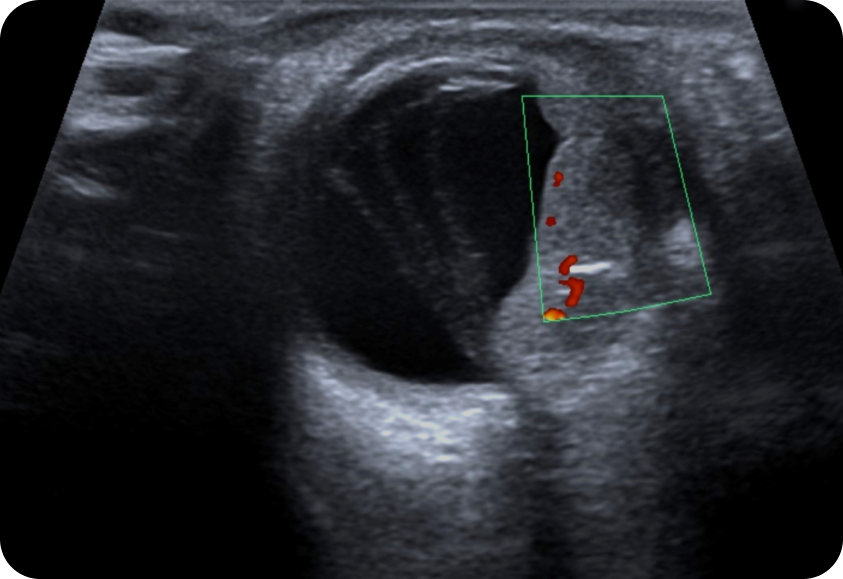

유방·갑상선 특화 검사 장비 보유

유방 전용 초음파, 맘모그래피, 조직검사 장비 등 특화된 진단 기기를 갖추고 있습니다.

전문 장비를 통한 정밀 검사로 정확한 진단과 안전한 치료를 제공합니다.